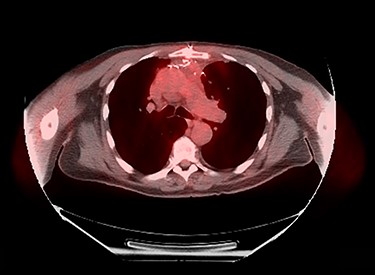

Patient’s post-operative course was notable for prolonged respiratory support due to phrenic nerve deficit. Patient’s respiratory failure resolved with 5-day course of intravenous antibiotics, spot diuresis and respiratory therapy. Patient was discharged home on post-operative day 10 day. Patient completed adjuvant radiation therapy at a total dose of 50 Gy in 25 fractions to the post-operative bed and anterior mediastinum. At 10-month follow-up, patient had no respiratory complaints with surveillance PET study showing no objective sign of tumor recurrence (Fig. 4).

Ten-month post-operative surveillance PET scan demonstrating no evidence of tumor recurrence.